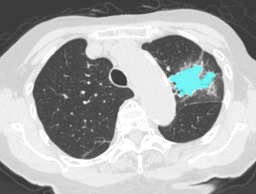

In this paper, we define partial annotation as an annotation format in which only one class is chosen for the annotation and only pixels belonging to the chosen class are annotated per image. For example, in Figure 1(a), although there is ground glass opacity in the image, only consolidation is chosen for annotation and pixels of consolidation are annotated. Partially annotated dataset is less informative for training, however, it is much easier to create compared to fully annotated dataset since annotators only need to focus on one class at a time during the annotation task.

Partially annotated datasets have been utilized previously [8, 9]. In this paper, we propose a new weak supervision technique that fully utilizes partially annotated dataset. Throughout this paper, each DLD pattern is represented or painted in the following colors (CON:cyan, GGO:yellow, HCM:red, EMP:green, NOR:brown.)

Statistics of our dataset are shown in Table 1 and typical images and their annotations for each DLD pattern are shown in Figure 1. In our partially annotated dataset, all the pixels in a slice were manually classified into two classes: dominating DLD pattern and other tissues. In other words, all the pixels in our dataset were assigned one of the labels from either of the two label sets, Lstrong={lCON,lGGO,lHCM,lEMP,lNOR}subscript𝐿𝑠𝑡𝑟𝑜𝑛𝑔subscript𝑙𝐶𝑂𝑁subscript𝑙𝐺𝐺𝑂subscript𝑙𝐻𝐶𝑀subscript𝑙𝐸𝑀𝑃subscript𝑙𝑁𝑂𝑅L_{strong}=\{l_{CON},l_{GGO},l_{HCM},l_{EMP},l_{NOR}\} or Lweak={lCON¯,lGGO¯,lHCM¯,lEMP¯,lNOR¯}subscript𝐿𝑤𝑒𝑎𝑘subscript𝑙¯𝐶𝑂𝑁subscript𝑙¯𝐺𝐺𝑂subscript𝑙¯𝐻𝐶𝑀subscript𝑙¯𝐸𝑀𝑃subscript𝑙¯𝑁𝑂𝑅L_{weak}=\{l_{\overline{CON}},l_{\overline{GGO}},l_{\overline{HCM}},l_{\overline{EMP}},l_{\overline{NOR}}\}. For example, in Figure 1(a), colored pixels were labeled as lCONsubscript𝑙𝐶𝑂𝑁l_{CON} and all the other pixels were labeled as lCON¯subscript𝑙¯𝐶𝑂𝑁l_{\overline{CON}}. In this paper, we call pixels of label lLweak𝑙subscript𝐿𝑤𝑒𝑎𝑘l\in L_{weak} and lLstrong𝑙subscript𝐿𝑠𝑡𝑟𝑜𝑛𝑔l\in L_{strong} as weakly annotated pixels and strongly annotated pixels respectively. Our pixel-wise annotations were created in the following steps. First, up to 3 slices were chosen for the annotation for each HRCT scan and for each slice, one representing DLD pattern was chosen by a radiologist. Second, three radiologists performed pixel-wise binary annotation (e.g. binary annotation between lCONsubscript𝑙𝐶𝑂𝑁l_{CON} or lCON¯subscript𝑙¯𝐶𝑂𝑁l_{\overline{CON}}) for each slice. Finally, the radiologists’ annotations were merged by taking majority classes for each pixel (i.e. pixels labeled as a DLD pattern by more than 2 radiologists became the corresponding DLD pixel). In addition to the DLDs annotation, lung fields were manually segmented under the supervision of radiologists and training and testing were conducted only within the lung fields.

Figure 1: Typical slices for each DLD classes. Slices of HRCT are shown in lung window setting (window-center=-600, window-width=1500) with annotated labels superimposed in transparent colors. Note that even if more than one DLD patterns existed, only one DLD pattern was chosen and annotated for a slice to facilitate the annotation process.